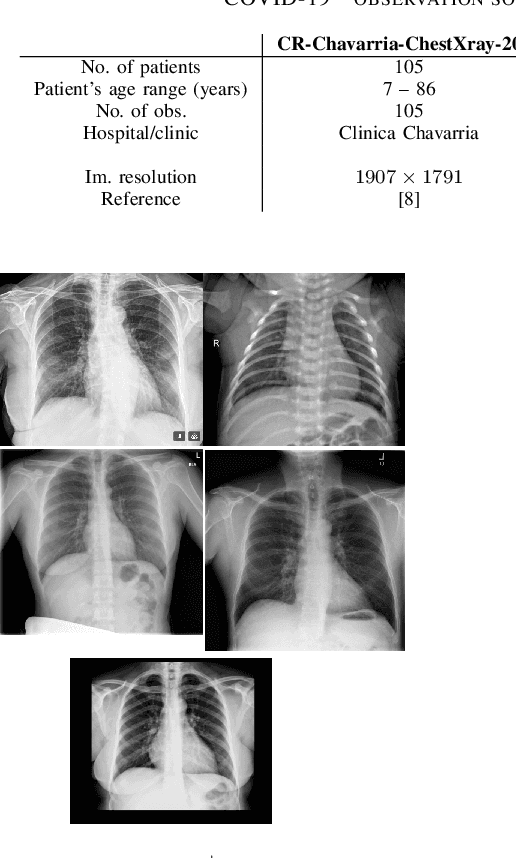

Abstract:The Corona Virus (COVID-19) is an internationalpandemic that has quickly propagated throughout the world. The application of deep learning for image classification of chest X-ray images of Covid-19 patients, could become a novel pre-diagnostic detection methodology. However, deep learning architectures require large labelled datasets. This is often a limitation when the subject of research is relatively new as in the case of the virus outbreak, where dealing with small labelled datasets is a challenge. Moreover, in the context of a new highly infectious disease, the datasets are also highly imbalanced,with few observations from positive cases of the new disease. In this work we evaluate the performance of the semi-supervised deep learning architecture known as MixMatch using a very limited number of labelled observations and highly imbalanced labelled dataset. We propose a simple approach for correcting data imbalance, re-weight each observationin the loss function, giving a higher weight to the observationscorresponding to the under-represented class. For unlabelled observations, we propose the usage of the pseudo and augmentedlabels calculated by MixMatch to choose the appropriate weight. The MixMatch method combined with the proposed pseudo-label based balance correction improved classification accuracy by up to 10%, with respect to the non balanced MixMatch algorithm, with statistical significance. We tested our proposed approach with several available datasets using 10, 15 and 20 labelledobservations. Additionally, a new dataset is included among thetested datasets, composed of chest X-ray images of Costa Rican adult patients